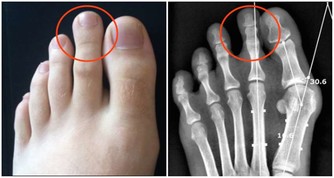

說到痛風,很多人第一印像是膝蓋、腳後跟、腳大拇指等地方疼痛,到醫院一查,尿酸高了!

痛風是由單鈉尿酸鹽沉積所致的晶體相關性關節病,與嘌呤代謝紊亂和(或)尿酸排泄減少所致的高尿酸血症直接相關,特指急性特徵性關節炎和慢性痛風石疾病。

痛風是長期嘌呤代謝障礙,導致體內長期尿酸增高,會在局部形成尿酸結晶,特別是下肢的足背小關節,會導致痛風性關節炎,或是直接形成痛風石,從而會刺激關節面引起反复的疼痛。其臨床特點就是高尿酸血症。但在疼痛急性發作期並不一定的尿酸最高時。